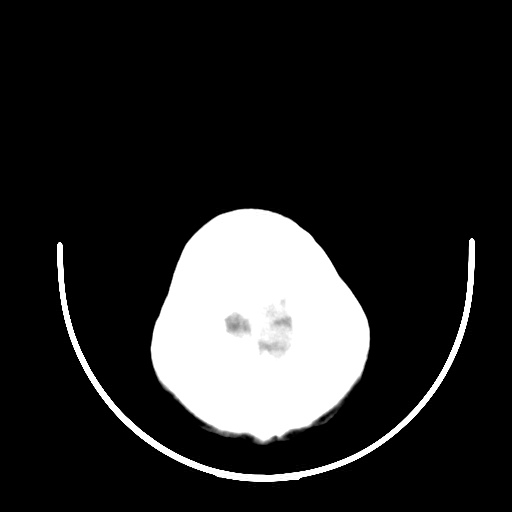

标题: CT16579:女 65岁间断性抽搐. [打印本页]

标题: CT16579:女 65岁间断性抽搐.

考虑右侧颞叶脑软化灶并脑穿通畸形;建议必要时行进一步检查。

右侧蛛网膜囊肿

右颞叶脑软化灶。余未见明显异常。

考虑右颞叶脑软化灶

右颞叶软化灶,右基底节区腔隙性脑梗塞;